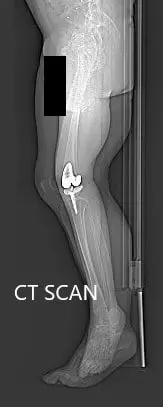

Preoperative topography CT scan images of the lower extremities

Preoperative topography CT scan images of the lower extremities - img 2

Preoperative topography CT scan images of the lower extremities.

A preoperative CT scan was obtained a few weeks prior to the procedure. Detailed models of the patient’s anatomy were constructed. Accurate bone cuts and offsets were determined to preplan the surgery. Disposable unique jigs and customized implants were made to match the patient’s anatomy.